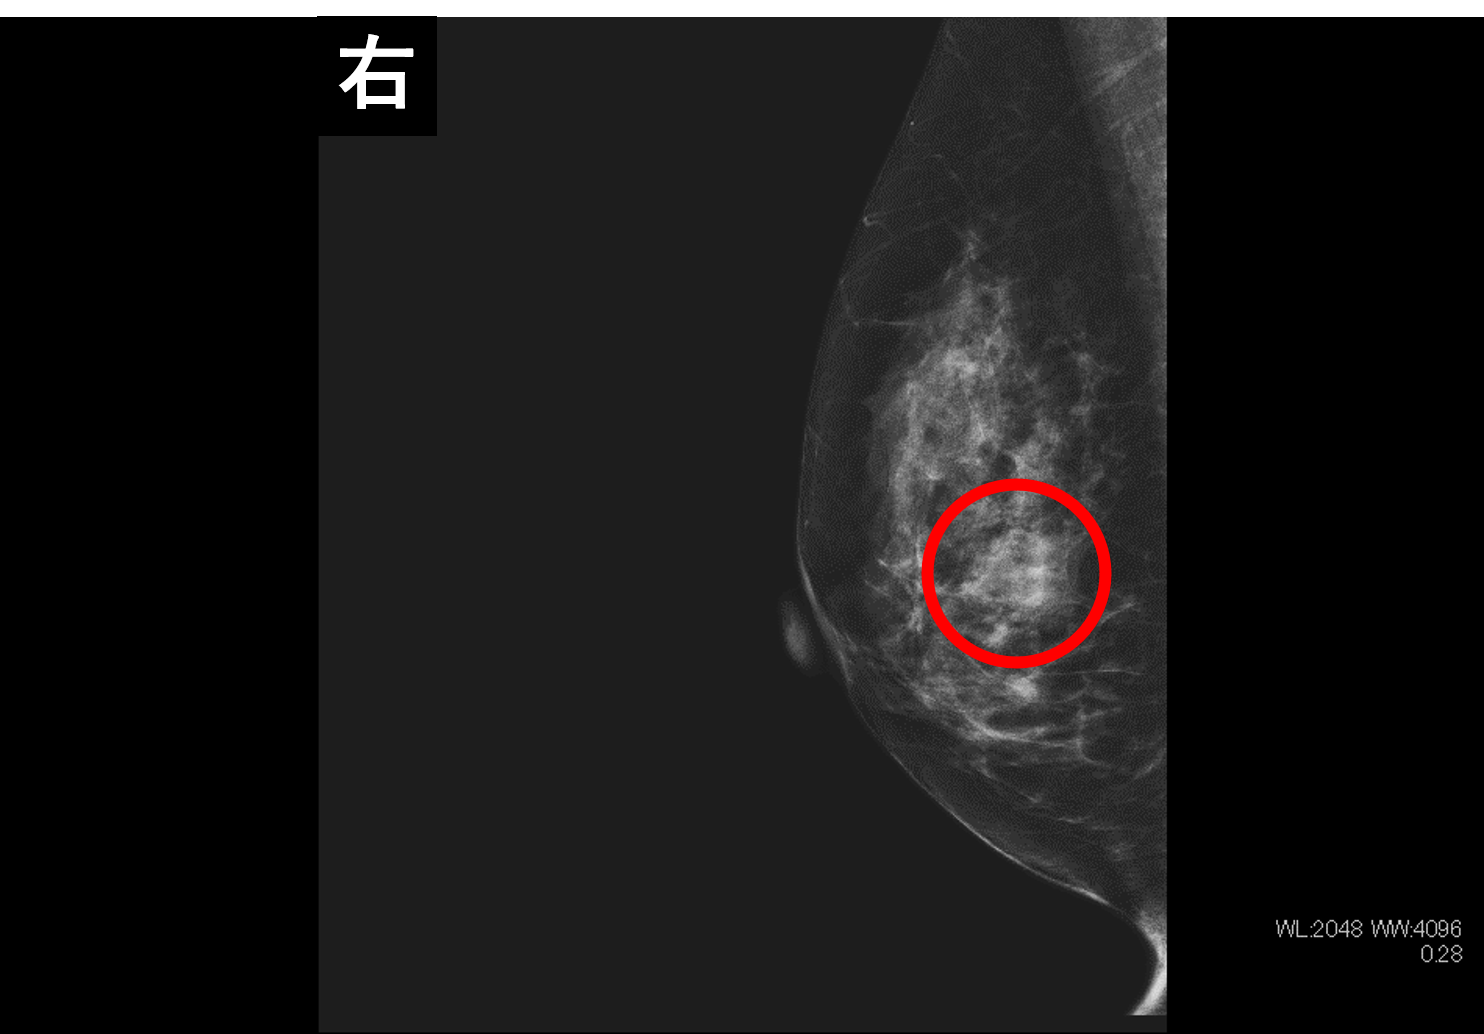

乳房専用のX線撮影検査になります。乳房全体を圧迫し、薄く伸ばした状態で撮影します。乳房を薄く伸ばすことで正常な乳腺の重さが少なくなり、腫瘤の形状や辺縁が観察しやすくなります。マンモグラフィは、乳房を触ってもわからないようなタイプの乳がん(石灰化病変)を描出することに優れています。

右乳房に腫瘤が2つ描出されている。